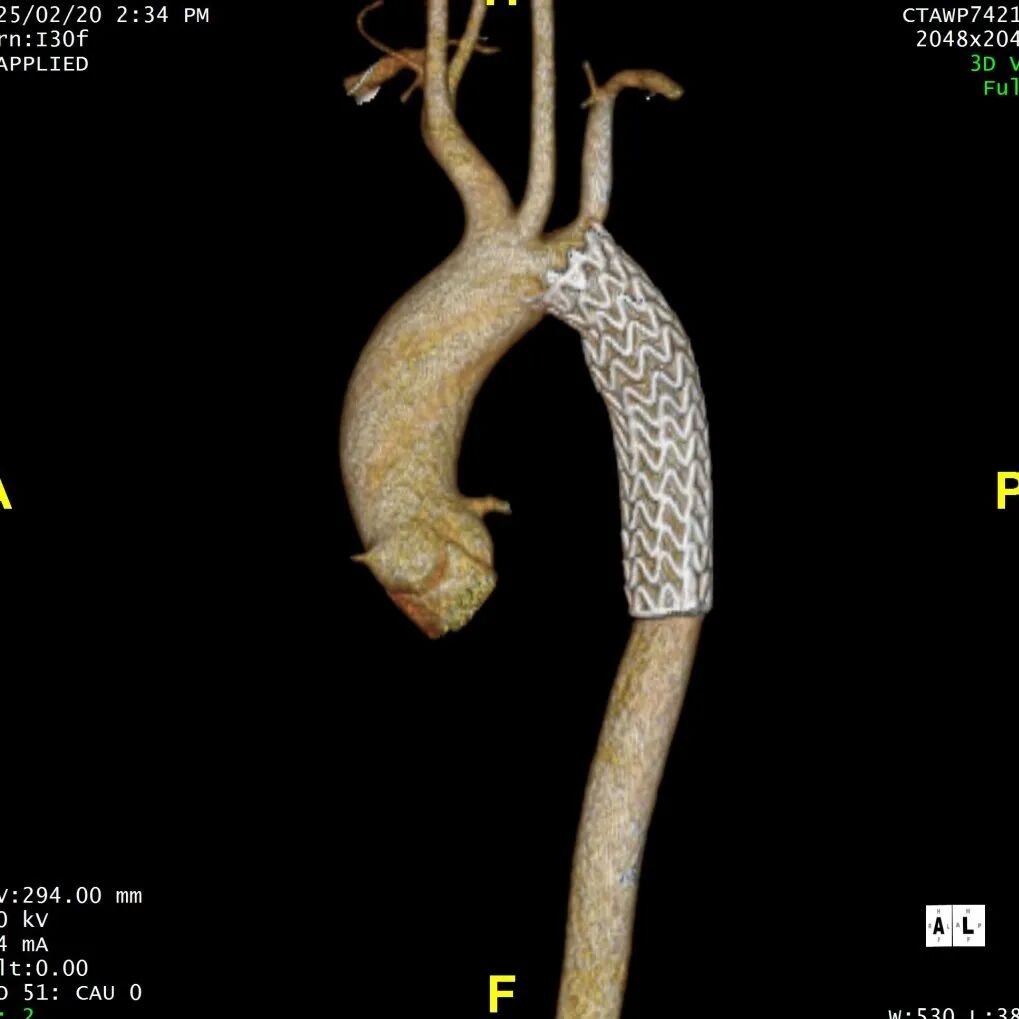

患者在半年后进行随访,支架形态良好,夹层隔绝完全。

术后复查CTA

术后3D重建